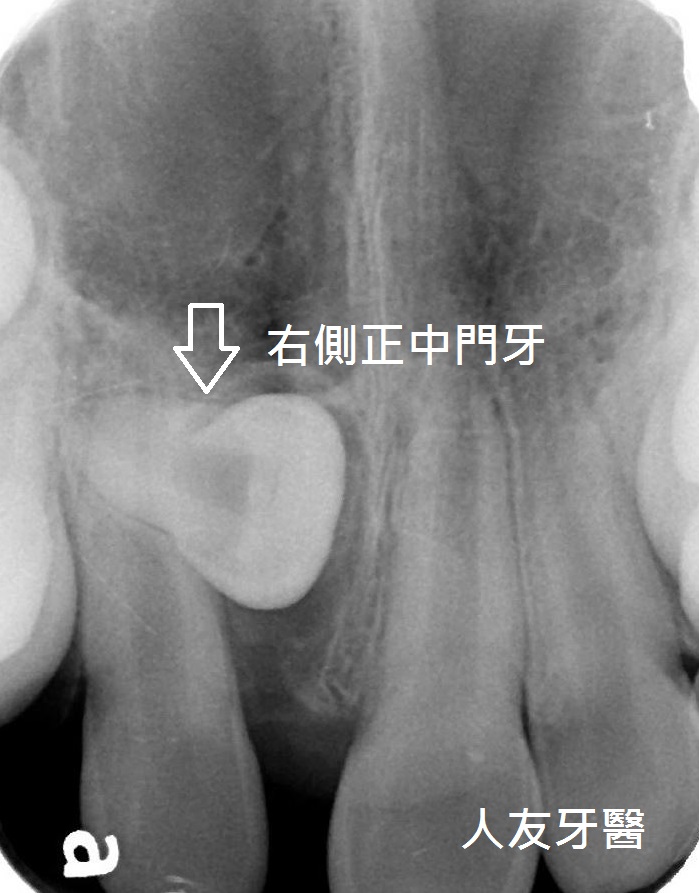

牙齒長不出來怎麼辦? part 1